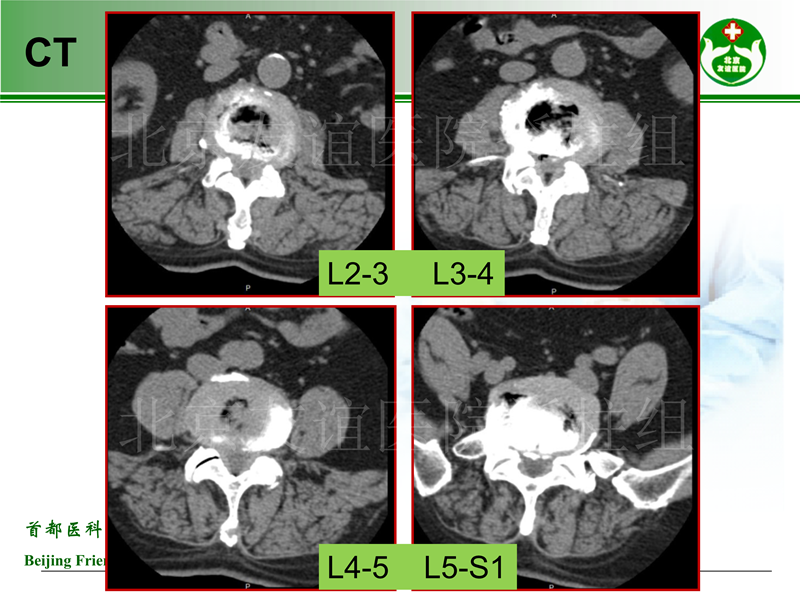

影像片: